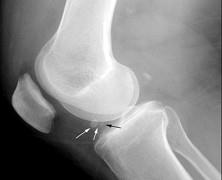

问题 女,65岁,右膝痛,活动受限,请结合图像,选出最可能的诊断 ( )

选项 A、类风湿关节炎 B、痛风 C、创伤性关节炎 D、退行性骨关节病 E、神经性关节病

答案 D